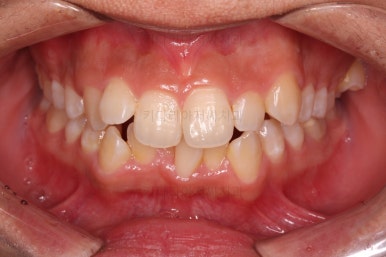

초진 시 입안의 모습입니다.

앞니가 많이 삐뚤고, 송곳니가 부각되어 덧니처럼 보이네요.

종료 시의 사진들을 전후 비교해 보겠습니다.

입매가 좋아졌고 입을 다무는 편안함도 좋아졌으며 치열이 가지런해졌으며 웃을 때 보이는 치열의 느낌도 좋고 교합도 잘 마무리 되었네요.